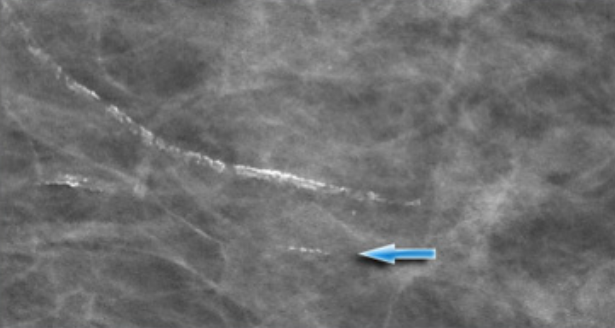

Структура злокачественных кальцинатов неоднородная, форма порой линейная или разветвленная, контуры нечеткие и неровные. Количество злокачественных кальцинатов может заметно увеличиваться и менять форму на последующих маммографиях.

Неправильной формы ветвистые микрокальцинаты в структуре злокачественной опухоли молочной железы